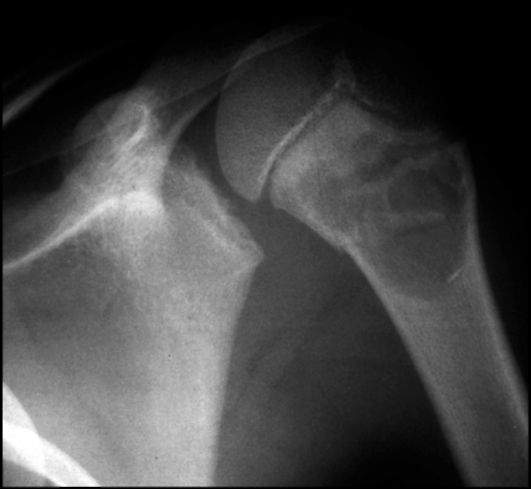

Процесс начинается с тщательного осмотра пациента, сбора жалоб и анамнеза. Затем проводится пальпация опухоли и окружающих тканей. После этого назначаются различные лабораторные и инструментальные исследования:

- общий анализ крови;

- рентгенография;

- ультразвуковое исследование плечевого сустава;

- магнитно-резонансная томография;

- пункция опухоли.

Эти диагностические мероприятия помогают установить причину кистозного образования, определить его местоположение и размеры, а также выбрать оптимальный метод лечения.